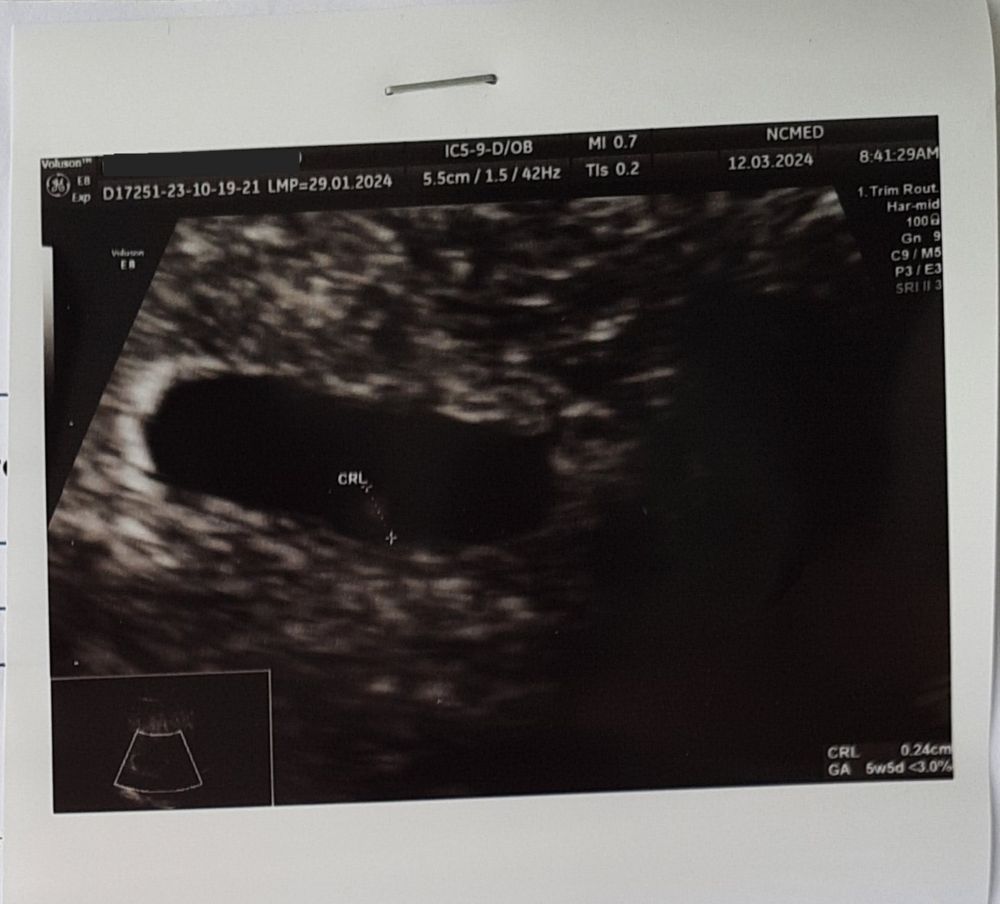

Первое УЗИ, 22дпп